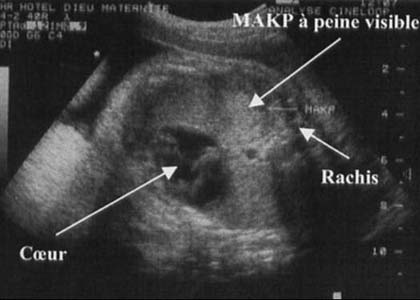

MAKP - microkystique